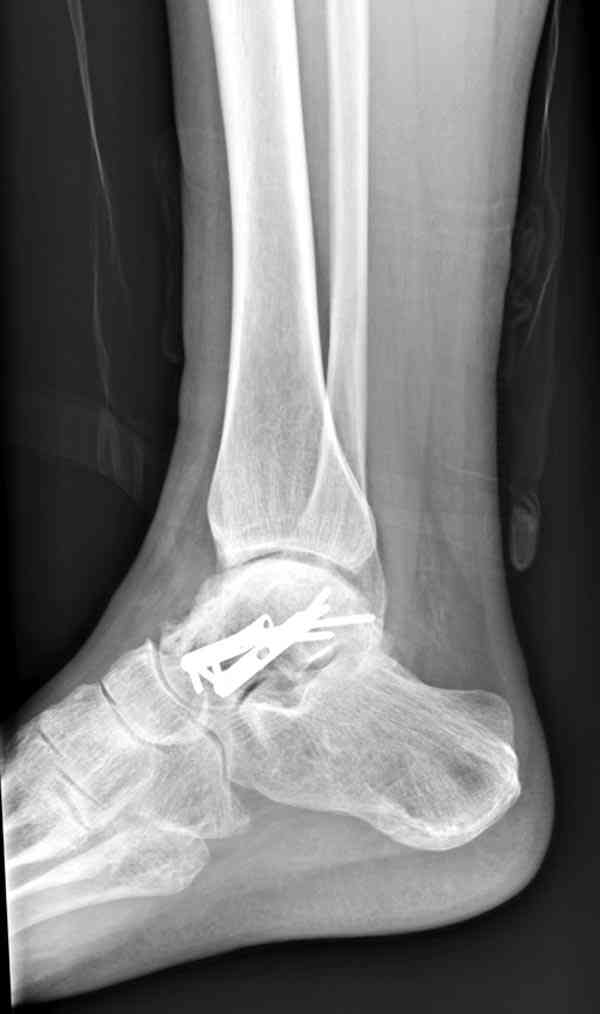

Случай с множественным оскольчатым переломом тарана оперированный из двойного доступа.

Через 2 мес.: